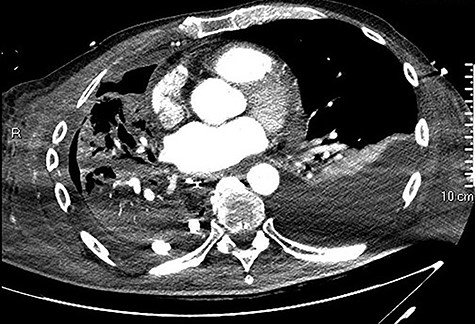

Initial CT showing a right hydropneumothorax after chest tube placement.

We present the clinical case of a 65 years old male patient submitted to totally minimally invasive Ivor Lewis esophagectomy after neoadjuvant chemo-radiotherapy for esophago-gastric junction adenocarcinoma (ypT2N0M0). A month after the surgery, the patient referred to our Emergency Department complaining acute dysphagia and asthenia. He presented with hypotension and tachycardia; laboratory blood tests revealed a

high PCR (291 mg/L) and the CT scan showed a right hydropneumothorax (Fig. 1). The first suspicion was an anastomotic leak and, in consideration of the hemodynamic instability and the severe septic state, the patient was submitted to emergency surgery. We performed a thoracoscopy with intraoperatively esophagogastroduodenoscopy which revealed a perforated prepyloric ulcer of the gastric tube. We therefore proceeded with accurate pleural toilette and closed the perforation with surgical stiches. At the end of the procedure, two thoracic drains and a naso-gastric tube with the distal end near the suture were placed. An additional naso-duodenum enteral feeding tube to ensure adequate nutrition was positioned. The patient was admitted in the Intensive Care Unit and supported with inotropic drugs, broad-spectrum antibiotics and proton pump inhibitor therapy. In the following days, the patient’s conditions improved allowing his extubation and his transfer to the surgical ward. Unfortunately, imaging and endoscopic check revealed a recurrent perforation. Considering the failure of the conservative approach, we decided to start the E-VAC Therapy on his 21st post-operative day (POD), using the Eso-SPONGE® System (B. Braun Surgical, S.A. Carretera De Terrassa, Rubi, Spain), firstly placed intraluminal because of the reduced size of the wall defect (Fig. 2). After three E-VAC replacements we did not observe any endoscopic or radiologic improvements. Moreover, on his 35th POD, due to a new impairment of vital signs, the patient underwent a second surgical treatment, with a new pleural toileting and another unsuccessful attempt of closing the conduit defect surgically. Considering the prolonged hospital stay, we placed a feeding jejunostomy. We proceeded with a new attempt of E-VAC, this time by placing it intracavitary (Fig. 3 and Fig. 4). The E-VAC was changed every 48–72 hours, reshaping the dimension of the sponge every time according to the size of the cavity. We observed a progressive reduction of the cavity size during the seriated endoscopic and CT evaluation. Considering the continuous improvement of patient’s clinical condition we discharged him after 84 days of hospitalization, with the E-VAC in place. The device replacement was carried on twice a week as an outpatient treatment, until its definitive removal (Fig. 5). The total duration of the therapy was 37 days with 13 E-VAC intracavitary interventions. Seven days after the device removal we performed an upper gastrointestinal X-Ray with oral contrast that showed no contrast medium leakage. The patient was therefore allowed to resume oral intake. At 6 months follow up the patient was in good clinical conditions; radiological test and endoscopy showed no abnormalities.